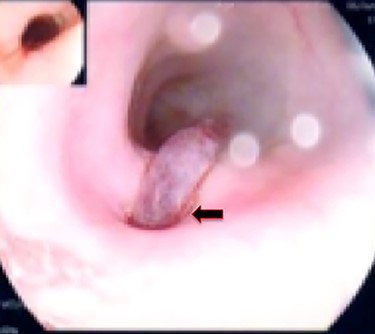

A 36-year-old male, involved in a minor motor vehicle accident while driving his car. He lost consciousness following a sudden onset of transient loss of vision which was not associated with palpitation or dizziness. His previous medical history revealed arterial hypertension and a corrected aortic coarctation with interposition graft at the age of 14. Pan CT scan was unremarkable except for thickening of the desending throacic aorta. His white blood count was very high (68 000 per cubic millimeter of blood). One day after the car accident, he developed nausea, hematemesis and melana. Upper GI endoscopy revealed blood in the stomach and distal esophafgus with no identifiable source of bleeding (Fig. 6). The patient developed massive hematemsis with hypotension requiring intubation and resuscitation. Another CT scan showed air pocket around distal aorta and contrast extravasation to the esophagus (Fig. 7). Another endoscopy revealed distal esophageal ulcer with clot extending toward the stomach (Fig. 8). AEF was suspected and then confirmed by aortogram. The fistula was treated by TEVAR (20 mm × 11.5 cm Valiant covered stent - Medtronic company, USA) followed by fully covered esophageal stent in the middle of the esophagus (Fig. 9).

First upper endoscopy blood within the stomach and duodenum; the esophagus image was not clear and no active bleed can be seen.